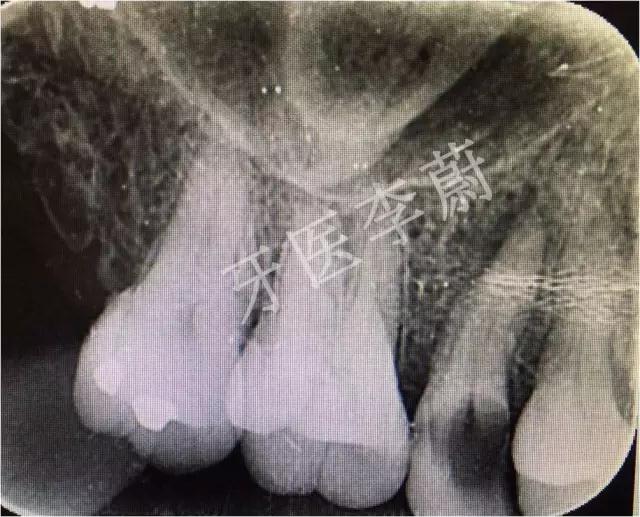

局部X牙片

15牙根管预备试尖片